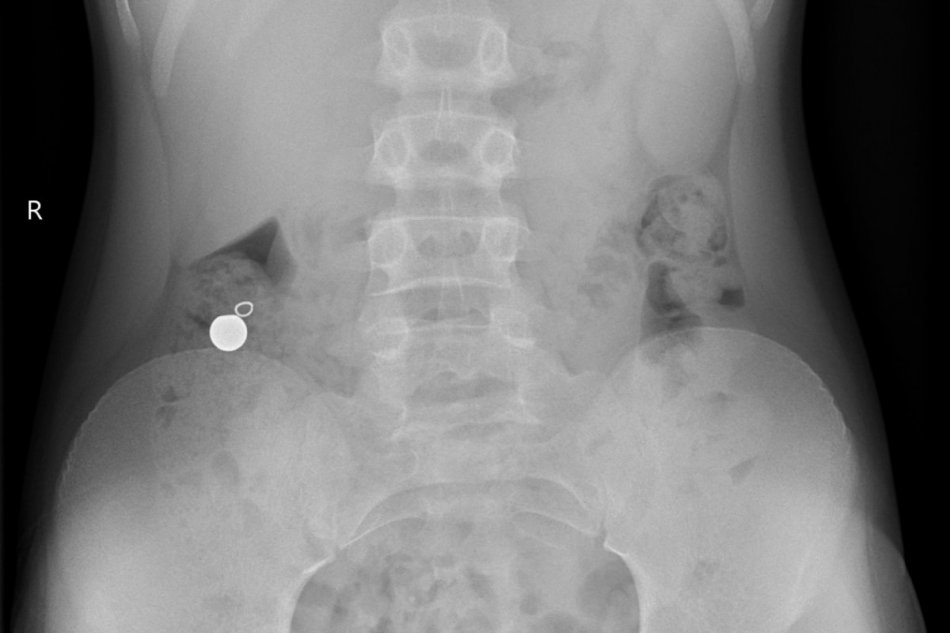

Ako informuje pražská Fakultná nemocnica Motol, prijali a ošetrili päť detí, ktoré sa podľa dostupných informácií inšpirovali výzvou na sociálnej sieti TikTok s názvom „TikTok piercing challenge“.

Deti pomocou guľôčkových magnetov chceli imitovať, že majú piercing napríklad v jazyku. Podľa nemocnice ale následne vo všetkých prípadoch došlo k nechcenému prehltnutiu magnetov.

„Pri prehltnutí viacerých magnetov alebo magnetu a kovového predmetu hrozí ich spojenie, ktoré môže k sebe pritiahnuť napr. žalúdok a črevo a spôsobiť jeho poškodenie alebo aj dokonca prederavenie (perforáciu), zápal a v niektorých prípadoch aj ohrozenie života,“ uvádza FN Motol.